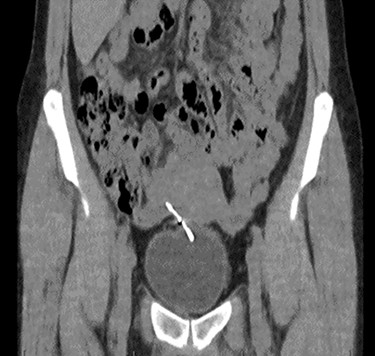

Computed tomography (CT) scan including a urographic phase revealed an IUCD in the vesico-uterine space, with one horn embedded into the bladder (Figs 2–4).

Coronal CT urinary tract image demonstrating the device lying between uterus and bladder, with one horn of the device embedded into the bladder.